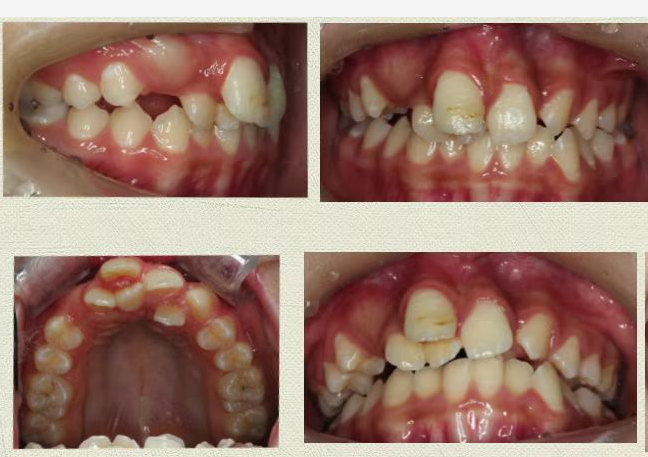

灵灵一张开嘴巴,见过了许多“乱牙”的林军主任医师也惊了一下,用“满口乱牙”来形容一点也不夸张,灵灵的牙齿不仅有好几处互相“挤压”,门牙位置还出现了多生牙(同一个位置长出了好几颗牙)。

根据灵灵的情况,口腔科专家团队为她制定了治疗方案——先拔除多生牙,排齐牙齿,再戴上矫正器矫正上下颌骨,改变嘴巴前突、下巴后缩的面容。

正畸前(左),灵灵下巴后缩严重;正畸后(右),明显改善